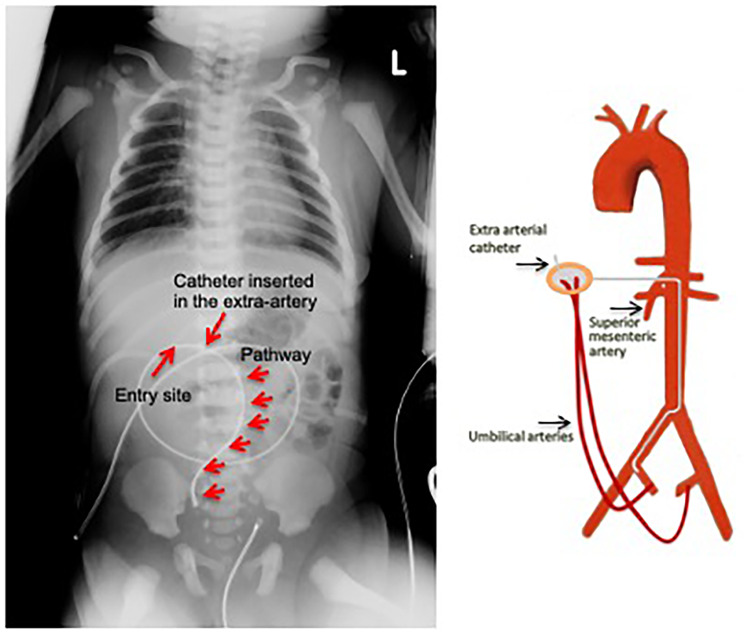

Case presentation: We present a unique case of a supernumerary patent umbilical artery in an asphyxiated term neonate, which resulted in the misplacement of the umbilical venous catheter in one of the three arteries. The diagnosis of artery cannulation was made through a comprehensive analysis of the patient's blood gases, the use of a pressure transducer to confirm the presence of a pulsatile arterial signal, and the interpretation of a chest X-ray. Subsequently, the catheter was removed without complication. A more detailed examination of the umbilical cord revealed the presence of three arteries and a vein, which was then successfully cannulated.

Conclusions: This case reinforces the notion that the umbilical cord may include more than three vessels, and that umbilical vein cannulation requires prior meticulous observation of the number of vessels to prevent misplacement of the catheter.